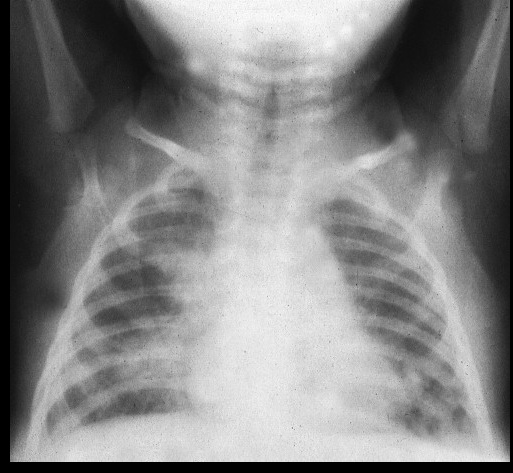

_Neonatal pneumonia and/or neonatal conjunctivitis occur due to untreated maternal Chlamydia trachomatis infection, as the baby is exposed to C. trachomatis in the vaginal canal during delivery.

Neonatal disease (conjunctivitis and atypical pneumonia)

Note: Because neonatal infections are acquired during passage through the birth canal, they usually involve these serovars, even though they occur “above the waist.”